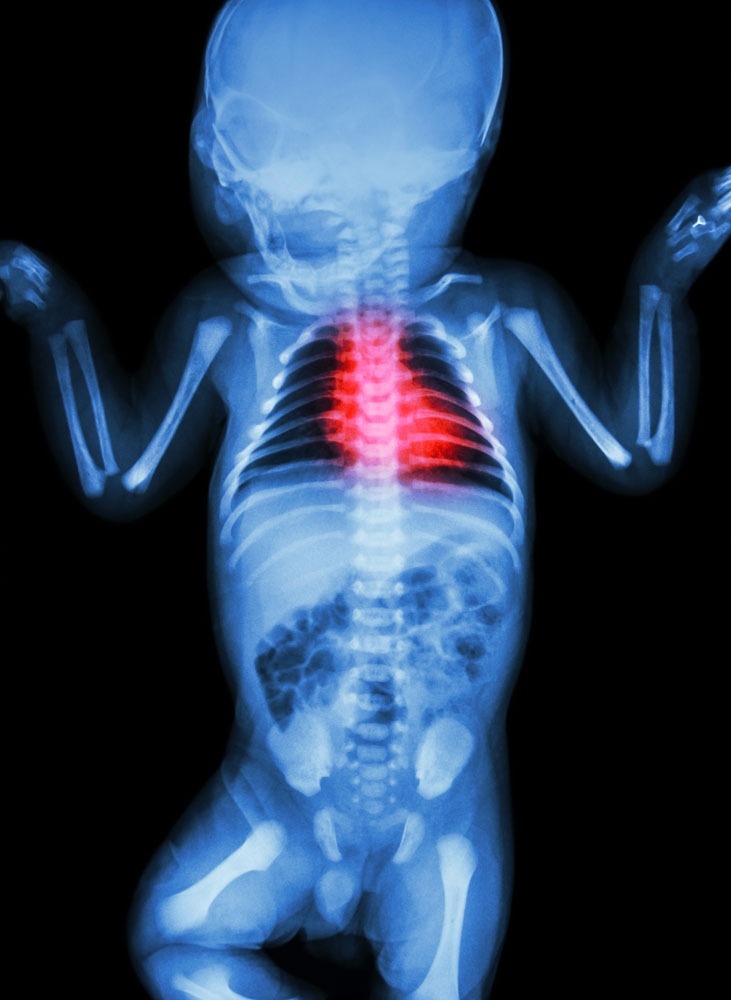

儿童那些疾病需要做X线检查

在医院,我们经常会遇到患儿家长唯恐X线伤及小儿身体而放弃检查,导致延误疾病的诊断与治疗。众所周知,X线对人体是有害的,大剂量的X线的确能损害人体部分白细胞,但目前国内外X线都是经过严格验收,所有设备的使用都在安全范围之内,而且检查时,医生会尽量减少照射剂量,以保护患儿身体健康。  那些儿科疾病需要做X线检查呢?

新生儿疾病

由于新生儿的生理特点,一般临床检查往往不能准确地判断其所患疾病,这样就会延误治疗,因此,若新生儿为早产、难产儿、或有生后窒息,患儿出现呼吸困难、面色青紫、口吐白沫、精神不好,应速到专科医院拍胸片检查。如发生新生儿出生后不能吃奶,并有持续性呕吐,吐粘痰,腹部红肿膨隆等情况,一定要去医院X线摄片帮助诊断与治疗。